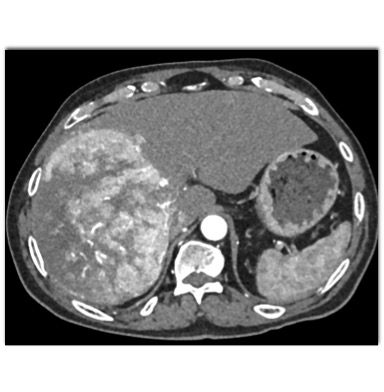

The most likely diagnosis in this case is?

hepatoma

hepatic adenoma

MCN (mucinous cystic neoplasm)

hemangioma